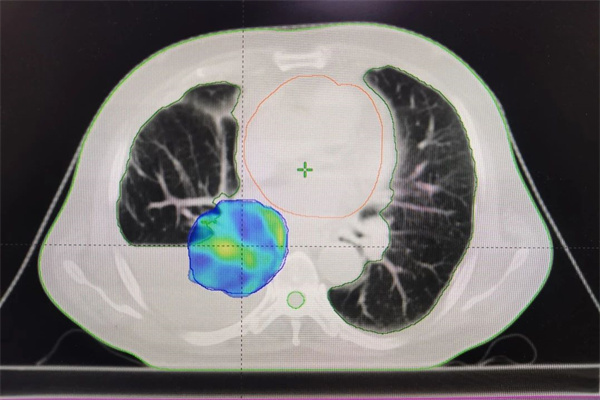

2024年右肺下叶肿物精准放疗计划

为确保最佳治疗效果,同时降低副反应,我们放疗团队仔细查阅了韩大爷7年前的放疗方案(针对右肺上叶)。经过全面的评估和讨论,我们决定为他量身定制新的放疗计划,针对现阶段右肺下叶的肿物进行精准放疗。在新的治疗方案中,我们对放疗计划不断优化进行剂量雕刻,以最大限度地减少对周围肺健康组织的损伤,并确保治疗的精确性和安全性。新的放疗计划一经制定,便立即启动了治疗程序。